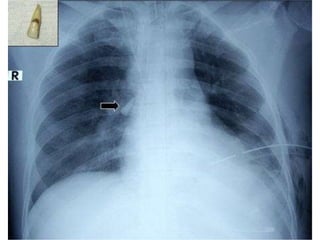

Avulsion

Where is the tooth?

Consider XR if “missing”

Reimplant or place tooth in physiologic

medium ASAP

Avoid traumatizing periodontal ligament

Chance of successful reimplantation inversely

proportional to time out of socket